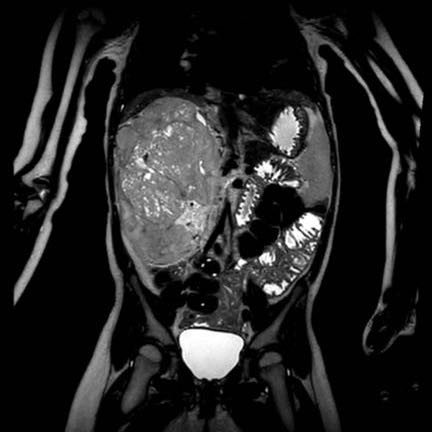

Ca lâm sàng 1

Hình ảnh chuỗi xung T2W mặt phẳng coronal cho thấy một khối u không đồng nhất ở thận trái với các thành phần nang nhỏ.

Khối u ngấm thuốc kém hơn so với phần nhu mô thận bình thường còn lại ở ngoại vi.

Các thành phần đặc của khối u cho thấy hạn chế khuếch tán rõ rệt (mũi tên).

Đây là u Wilms ở bé trai năm tuổi. Hóa trị tiền phẫu được thực hiện theo phác đồ Umbrella của SIOP-RTSG, sau đó tiến hành cắt thận.